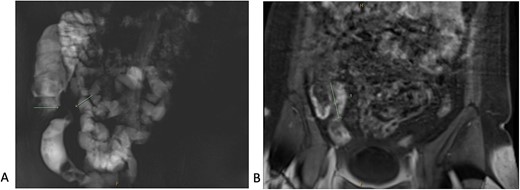

A 34-year-old female presented with colicky episodic abdominal pain and symptoms suggestive of subacute small bowel obstruction in the setting of known stricturing CD. Her symptoms were poorly controlled on multiple medications—Azathioprine, Mesalazine, Adalimumab and Budesonide. She had no previous history of abdominal surgery or gynaecological pathology. She had twice undergone endoscopic balloon dilatation of a terminal ileal stricture with short-lived symptomatic relief. Contrast-enhanced computed tomography (CT) of the abdomen and pelvis showed a short segment of acute inflammation of the terminal ileum (Fig. 1) and an incidental right adnexal cyst. Pelvic ultrasonography was normal. Magnetic resonance enterography confirmed stricturing CD with two segments of inflammation of the terminal ileum (lengths of 5 and 3.8 cm) approximately 5 cm from the ileocaecal valve (Fig. 2).

Magnetic resonance enterography demonstrating strictures of the small bowel (A) in a segment of terminal ileitis with acute inflammation (B).